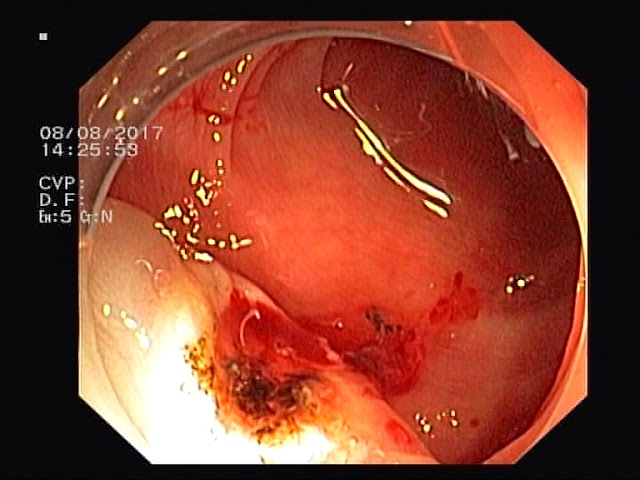

Ворсинчатая аденома формируется на кишечной поверхности. На ощупь отличается мягкой структурой, а в строме отмечают воспаления. Внешний вид похож на цветную капусту. Комбинация с эпителиальной частью, слизистой и фиброзной ткани становится основой для образования опухоли. Чаще всего рак распространяется по всему верхнему слою кишки. Стандартная величина – до 2-3 см, изредка – 9 см (один из опаснейших видов аденом). В 40% событий она видоизменяется в злокачественную.

- Ректороманоскопия. Оцениваются нижние отделы толстого кишечника. Через задний проход вводят камеру. Действенна при расположении рака в прямой или сигмовидной кишке. Для анализа берутся фрагменты эпителия.

- Колоноскопия. Похожа на предыдущий метод: оценивает ситуацию в толстой кишке, доходя до труднодоступных участков. В конце изымается кусочек ткани для патоморфологического обследования.